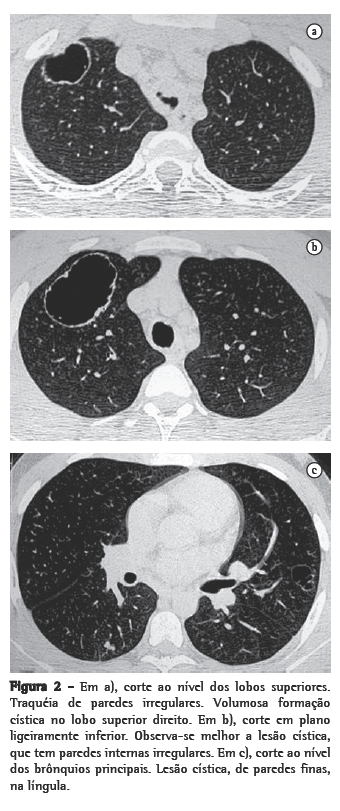

Nos 8 casos foram observadas na TC formações polipóides na traquéia. Em 1 deles, identificou-se também uma lesão em brônquio principal. Sete pacientes mostravam comprometimento do parênquima pulmonar. Em todos foram observadas lesões nodulares escavadas, com contornos internos irregulares, e paredes de espessuras variadas, com aspecto multilobulado em 6 casos, e com confluência das lesões em 5 deles (Figuras 1 a 5). Nódulos sólidos foram vistos em 6 pacientes, Em apenas 1 dos casos foram vistos níveis líquidos. As lesões predominaram nas bases em 3 pacientes, nos terços médios em 2, e em 2 não havia predomínio de distribuição. Em 1 dos pacientes, foi observada associação com massa, e em outro, com consolidação. Neste último paciente (Figura 5) foi constatada degeneração maligna em múltiplas lesões. Sinais de aprisionamento aéreo também foram observados em 1 caso. Em nenhum deles detectou-se linfonodomegalia ou derrame pleural.

A TC, particularmente com aquisição volumétrica (espiral), é superior às radiografias de tórax no reconhecimento de nódulos ainda pequenos, nas fases iniciais de disseminação pulmonar, por sua melhor caracterização e visualização de vegetações nodulares traqueobrônquicas. Os achados tomográficos incluem estreitamento nodular, focal ou difuso, da via aérea. Os nódulos crescem na superfície mucosa, e sua extensão intraluminar é melhor avaliada por TC.(3) São alterações facilmente correlacionadas à doença quando se dispõe da história clínica de papilomatose.(4) Outros achados relacionados à obstrução das vias aéreas e/ou infecções associadas são atelectasias, consolidações, aprisionamento aéreo e bronquiectasias.(2-4) Na nossa casuística, formações polipóides na traquéia foram observadas em todos os exames tomográficos. Sete pacientes mostravam comprometimento do parênquima pulmonar, caracterizado por lesões nodulares escavadas, com contornos internos irregulares, e paredes de espessuras variadas, com aspecto multilobulado e tendendo à confluência. Nódulos sólidos foram vistos em 6 pacientes. Em nenhum deles detectou-se linfonodomegalia ou derrame pleural.